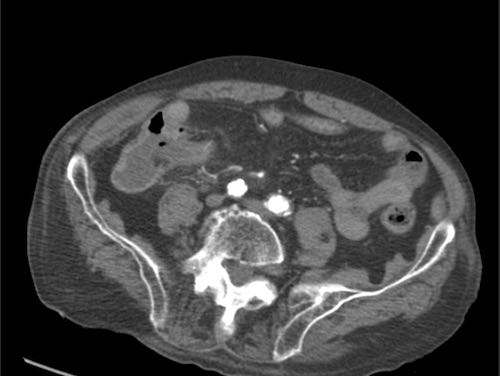

Bệnh nhân nam 85 tuổi này nhập viện với đau khu trú dữ dội, viêm phúc mạc khu trú và CRP 200, lâm sàng nghi ngờ viêm ruột thừa.

Siêu âm cho thấy một vùng nhỏ khu trú gồm mỡ tăng âm bị viêm (đầu mũi tên), chứa một ít dịch (*) và một phản âm khó lý giải (mũi tên trắng).

Chẩn đoán siêu âm dự kiến là viêm phần phụ mạc nối với vùng xuất huyết trung tâm nhỏ.

CT xác nhận thâm nhiễm mỡ khu trú và phát hiện thêm một bóng khí cũng như dày thành nhẹ của một quai ruột non lân cận.

Áp dụng từ gợi nhớ PSI-ABCD, tất cả các nguyên nhân đều được loại trừ, ngoại trừ dị vật sắc nhọn.

Sau khi tìm kiếm có chủ đích, một xương cá được phát hiện tại manh tràng (mũi tên xanh lá trên CT).

Rõ ràng, xương cá này đã gây ra thủng, và sau đó được đẩy đi bởi nội dung ruột non. Bệnh nhân được điều trị bằng kháng sinh đơn thuần và hồi phục hoàn toàn.